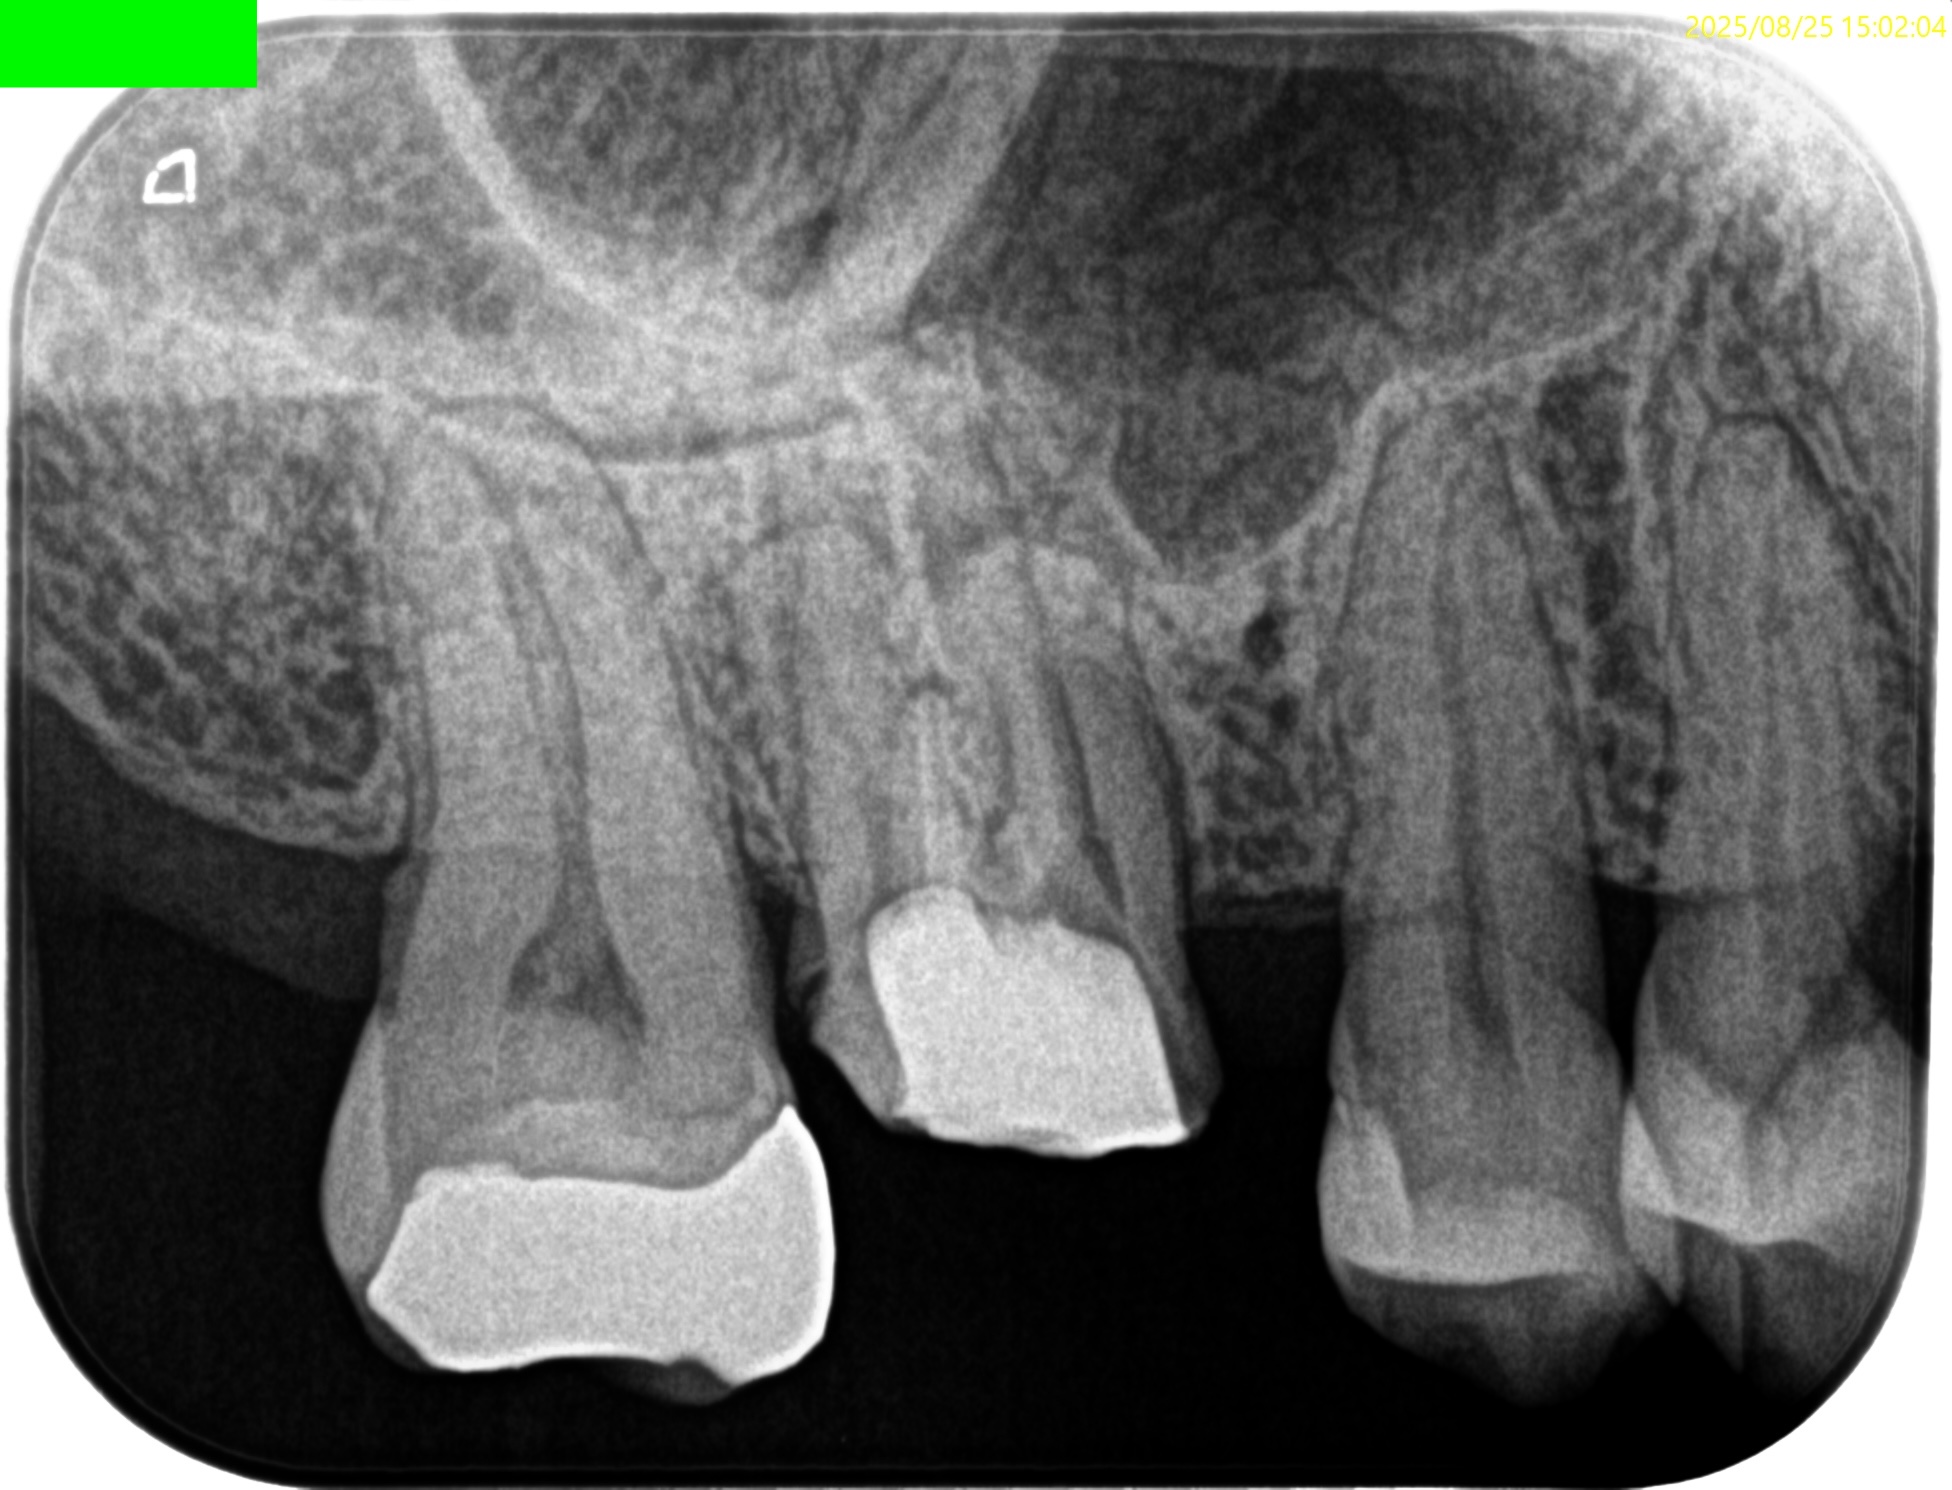

Pre-op Endo test(2025.8.25)

MB

DB

P

MB,DB,P全ての根管に根尖病変がある。

PのP側皮質骨はかなり減少している。

これが歯周病が原因か?と言えば、

術前の検査で歯周ポケットが正常値(Within Normal Limit)なため、恐らくエンドが原因でこのようになっているのだろう、と推測できる。